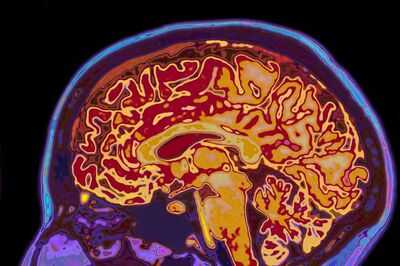

You might have assumed that all brains are roughly the same size. Butscientists suggest this isn't always the case – in fact, the shape of our brain could potentially help detect early signs of dementia.

New research from the University of California explored this concept, analysing over 2,600 brain scans of adults aged 30 to 97. Remarkably, they observed that 'uneven shaping' was particularly prominent in older adults experiencing cognitive decline, which could indicate new markers for identifying dementia risk.

Senior author Niels Janssen explained: "Most studies of brain ageing focus on how much tissue is lost in different regions. What we found is that the overall shape of the brain shifts in systematic ways, and those shifts are closely tied to whether someone shows cognitive impairment."

In the fresh analyses, scientists observed that older adults experiencing cognitive decline showed greater expansion in the 'inferior and anterior parts of the brain', while the 'superior and posterior regions' contracted inward. Adults with 'poorer reasoning' skills were also frequently noted to have 'more pronounced posterior compression', referring to something pressing upon the back.

However, according to the team, one of the study's most striking implications was understanding the 'potential impact of shape changes with age on the entorhinal cortex'. This specifically describes a small but crucial memory base located in the brain.

The study indicates that these shape alterations might physically push this vulnerable area nearer to the rigid base of the skull. The entorhinal cortex is also among the initial regions where tau, a harmful protein associated with Alzheimer’s disease, starts to accumulate.

Co-author Dr Michael Yassa also explained: "This could help explain why the entorhinal cortex is ground zero of Alzheimer’s pathology. If the ageing brain is gradually shifting in a way that squeezes this fragile region against a rigid boundary, it may create the perfect storm for damage to take root.

"Understanding that process gives us a whole new way to think about the mechanisms of Alzheimer’s disease and the possibility of early detection." Overall, scientists think that gaining a better understanding of how brain shape changes could assist in understanding the mechanisms of risks, even during the earliest stages of the disease.

Dr Yassa continued: "We’re just beginning to unlock how brain geometry shapes disease. But this research shows that the answers may be hiding in plain sight – in the shape of the brain itself."